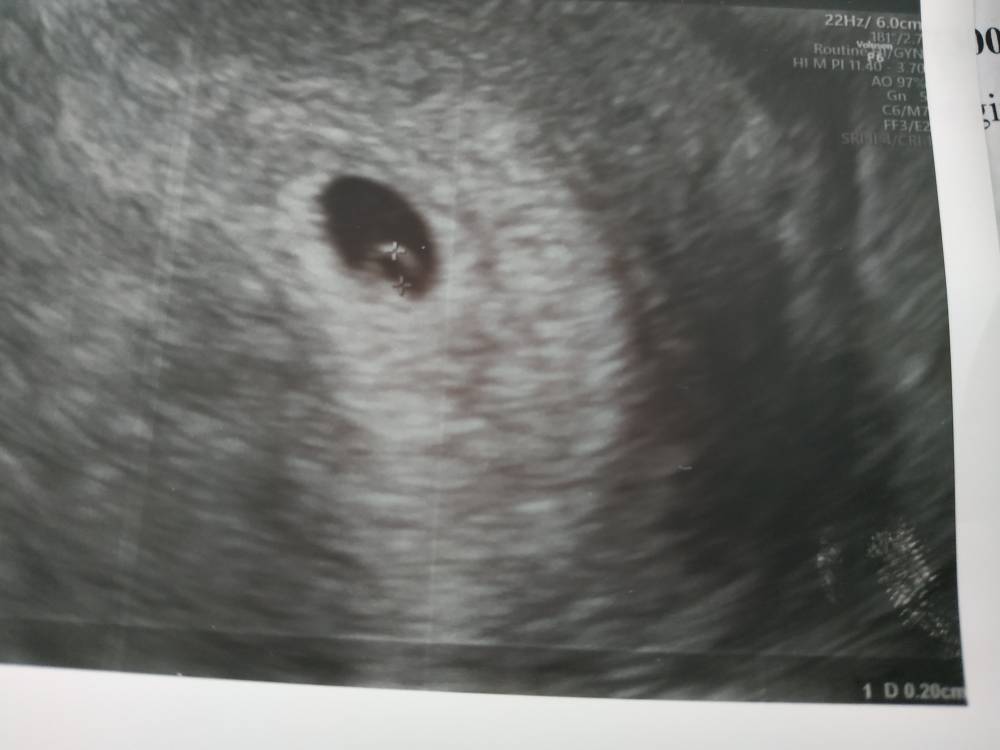

U mnie dzisiaj 5t4d i nie miałam zarodka, ale lekarz mówił , ze wszystko jest dobrze. Za dwa tygodnie mam już zobaczyć serduszko [emoji3590]Zobacz załącznik 1015892Zobacz załącznik 1015893